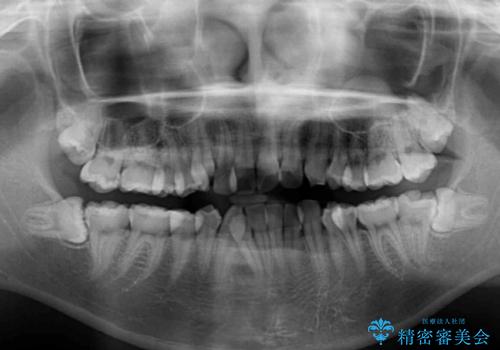

- 八重歯やデコボコをインビザラインで治療したいとのことで来院された患者様です。

インビザライン単体で治療を行うには叢生が強いと判断されたため、事前にワイヤー装置で抜歯矯正を行い、ある程度改善してからインビザラインにて仕上げていくこととしました。